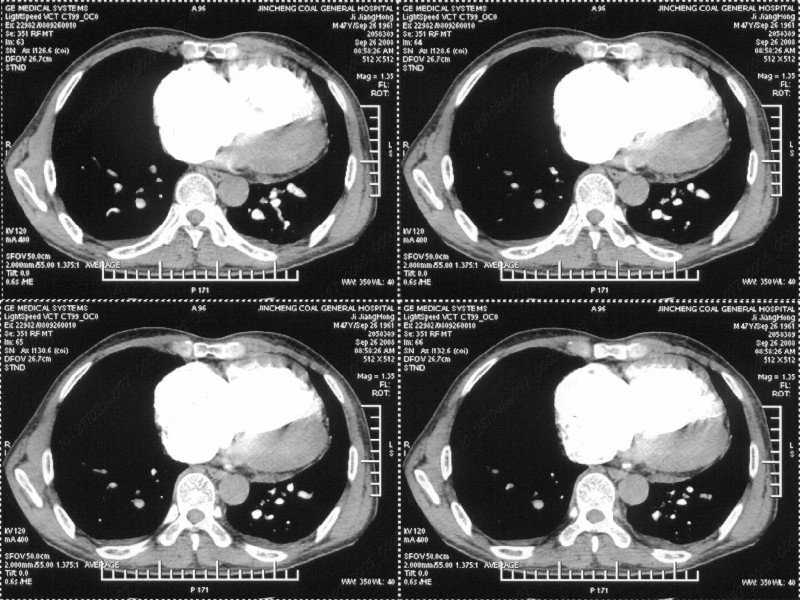

男性,47岁。胸部不适一年,ct检查发现右胸膜下结节。http://www.radida.com/bbs/forum.php?mod=viewthread&tid=46094

汇报临床诊断:右肺动脉分枝栓塞

右肺静脉充盈缺损,左心房体积小,右肺动脉远端动脉充盈缺损,右肺血管影细小,考虑;右肺动脉远端栓塞.

病灶周围似有纤维化征像,增强明显强化,但中央可见点状低强化区,考虑慢性病变可能如炎性假瘤等,病灶边缘部分毛糙有切迹,双侧胸腔少量积液影,不除外恶性

右下肺前胸膜下小结节,强化不明显。建议定期观察!